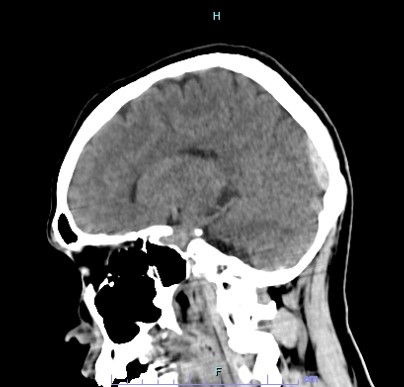

頭部に外力が加わることで、頭蓋骨とその内側にある脳をおおう硬い膜(硬膜)の間に出血し、形成された血腫によって脳が圧迫される状態です。多くは頭蓋骨の線状骨折や陥没骨折にともなって発生します。

■CT検査:頭部CT検査で評価します。頭蓋骨骨折の状況、ならびに硬膜外血腫の場所・血腫量、脳への圧排程度を評価することができます。数十わから数時間の経過で急激に症状が悪化することもあり、その都度CTによる評価を行い、手術が必要か検討する必要があります。